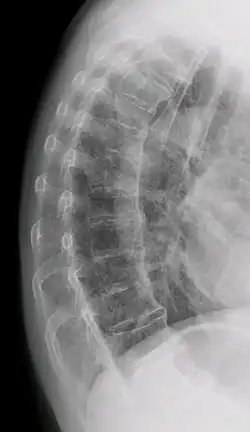

"Melted candle wax" appearance of calcification and ossification in diffuse idiopathic skeletal hyperostosis (DISH). Note the preponderance on the patient's left side (right side of image). -